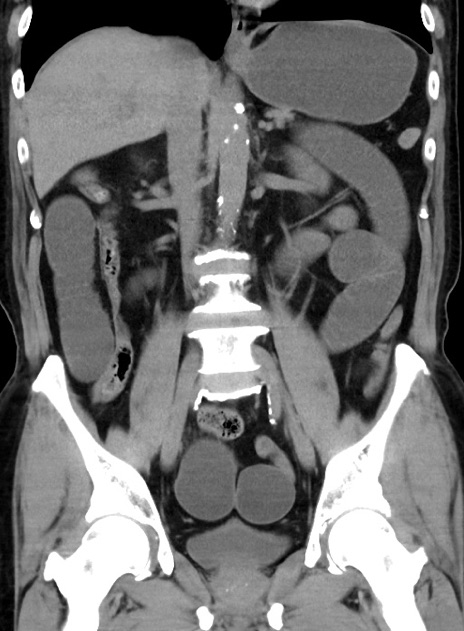

症例38(冠状断像)

【症例】70歳代 男性

【主訴】腹痛・嘔吐

【現病歴】昨晩より、嘔吐・腹痛あり。今朝になっても嘔吐あり。来院。

【既往歴】心臓バイパス手術、開腹胆摘、腸閉塞

【身体所見】BP 107/71mmHg、HR 116/min、腹部:平坦、軟、下腹部に軽度圧痛あり。反跳痛なし。

【データ】WBC 15100、CRP 0.32